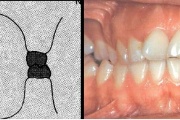

Sügav hambumus